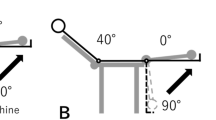

After a few minutes of warming up, subjects performed eccentric exercise of the hamstring muscles with the right leg using a plate-loaded knee-flexion machine (Prone Leg Curl; Nautilus, USA), which was adjusted to 120% of the 1 repetition maximum (1RM).

Subjects were instructed to lower the weight from a knee-flexed position (100°) to a knee-extended position (0°) in 3 s, maintaining the lowering velocity as constant as possible by following the examiner’s counting of “0” for the beginning and “1, 2, and 3” for the movement with planter flexion of the ankle to reduce the contribution of the gastrocnemius muscle. Subjects were verbally encouraged to generate maximal force at the starting position and to resist maximally against the knee-extending action throughout the range of motion. The weight was raised after each eccentric repetition by an examiner; therefore, the overall exercise task was eccentric only for the subject. This exercise was repeated for five sets of 10 repetitions each, with at least a 3-min rest between sets.